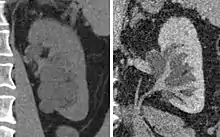

Massive hydronephrosis as marked by the arrow.- Renal ultrasonography of hydronephrosis[14]

- Stone causing hydronephrosis[14]